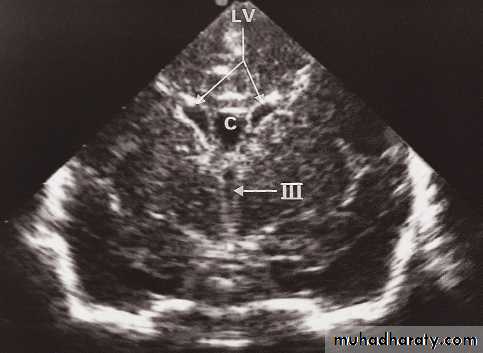

Neurosonography

• Simple to scan the heads of neonates and young babies to obtain images of the ventricular system and the adjacent brain.• Scanning is best done through an open fontanelle where there is no bone to impede the transmission of ultrasound.

• Little discomfort is caused to the baby and the procedure is readily carried out even on ill babies in intensive care units.

• Neurosonography has proved particularly useful in detecting intracerebral haemorrhage and the ventricular dilatation that may follow. It has also been used to demonstrate the presence and cause of other forms of hydrocephalus and congenital abnormalities of the brain.